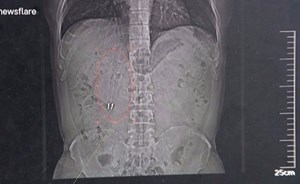

قام جراحون في أحد المستشفيات الصينية بإخراج قلمين من معدة رجل صيني يدعى وانغ، بعد أن بقيا في جوفة لمدة 36 عاماً. وقال…